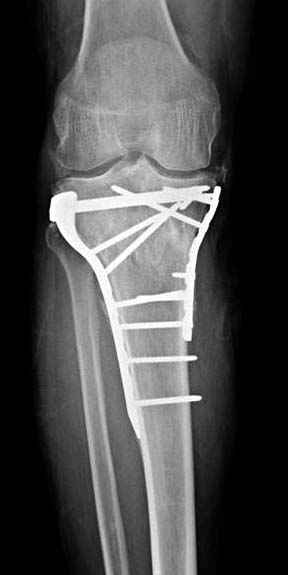

Решили выполнить остеосинтез штифтом и внутрисуставного перелома пластиной и винтами. Жду мнения! Зачем мне оправдываться-я же не преступник. Диалогом называется...

Отдельные переломы тибиал плато и перелом проксимальной трети большеберцовой кости отличаются от переломов тибиал плато с вовлечением диафиза. Здесь перелом тибиал плато типа Schatzker VI, полученный в результате высокоэнергетической травмы. Перелом метафиза образовал отрыв суставной поверхности от диафиза с вовлечением медиального и латерального мыщелков. Двухмыщелковые переломы из-за укрочения опасны развитием компартаментального синдрома, повреждением латерального мениска и связок.

При переломах одного из мыщелков тибиал плато+дополнительный перелом проксимальной трети большеберцовой кости можно применить комбинированный вариант фиксации, т.е. мыщелок винтами или пластиной, а для диафиза можно установить гвоздь. В данном варианте потеряно преимущество гвоздя , из-за серьезной травмы суставной поверхности нельзя нагружать ногу несколько месяцев. А без нагрузки гвоздь просто заполнитель пространства внутри кости!

На вашем место я бы подождал с фиксацией до готовности кожных покровов, и за это время можно было подобрать соответствующий фиксатор, т.е более длинная пластина снаружи и медиальная пластина на апексе перелома как подпорка. Здесь приемлем как раз минимальный доступ.

Имеющаяся импрессия не потребовала пластики - достаточным оказалось поднять отломок

Если там действительная импрессия, пустое место без структуральных заполнителей, кость или синтетические материалы, не восстановится, а образуется коллапс, и ось конечности поведет после нагрузки. Кроме того там возможно "болт стяжка"?, в медиальной стороне выступает за кортекс, можно было укоротить! Потом создается впечатление, что не соответствуют мыщелки большеберцовой и бедренной костей? Покажите снимок.

Здесь пару случаев для сравнения,...в первых 1-4 слайдах метод фиксации одним фиксатором, как видно после 8 месяцев сохранилась ось. С 5 по 9 вариант двумя пластинами...

Согласен с постами докторов Кульджанова и Волны. В данном случае мы не отмечаем признаков тщательного предоперационного планирования, что сказалось на характере принятого решения и его результате. В нашей клинике, мы бы использовали длинную блокированную пластину по латеральной поверхности, через проксимальное окно отрепонировали бы суставную поверхность, через дистальное фиксация 3-4 винтами в с/3 б/берцовой кости. По медиальной поверхности в качестве поддержки - 1/3 трубчастая или реконструктивная пластина. С большой долей вероятности использовали бы костную аутопластику.